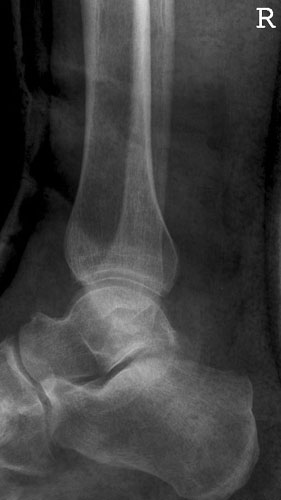

OSG a.p.

Fehler

Leichte Außenrotation des Fußes. Die laterale Kante der distalen Tibia springt besonders markant vor und verdeckt teilweise den Schaft der Fibula.

Abhilfe

Fuß weiter nach innen drehen lassen, bis beide Malleolen auf einer Höhe parallel zum Film stehen.